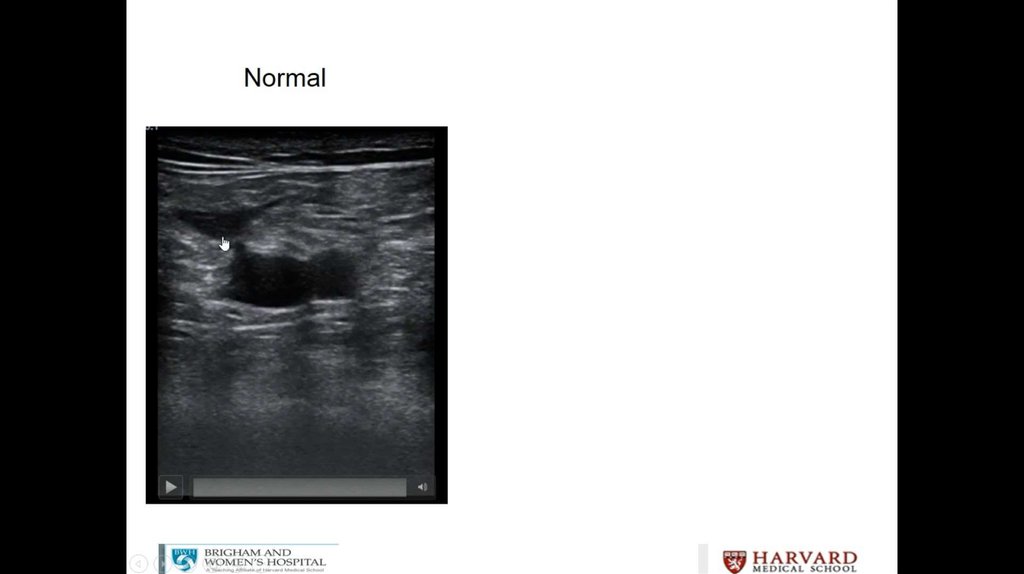

Litrasound in the ICU: What Every Intensivist Should Know